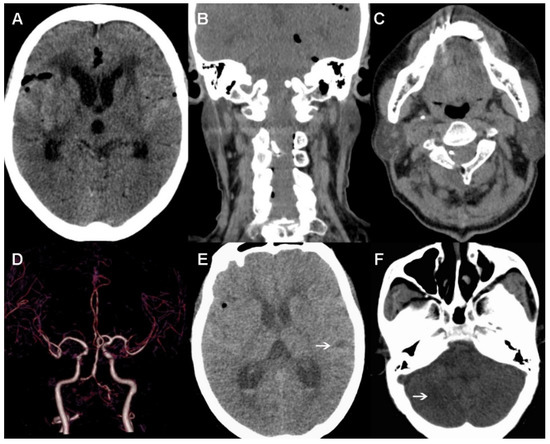

2. Case Presentation